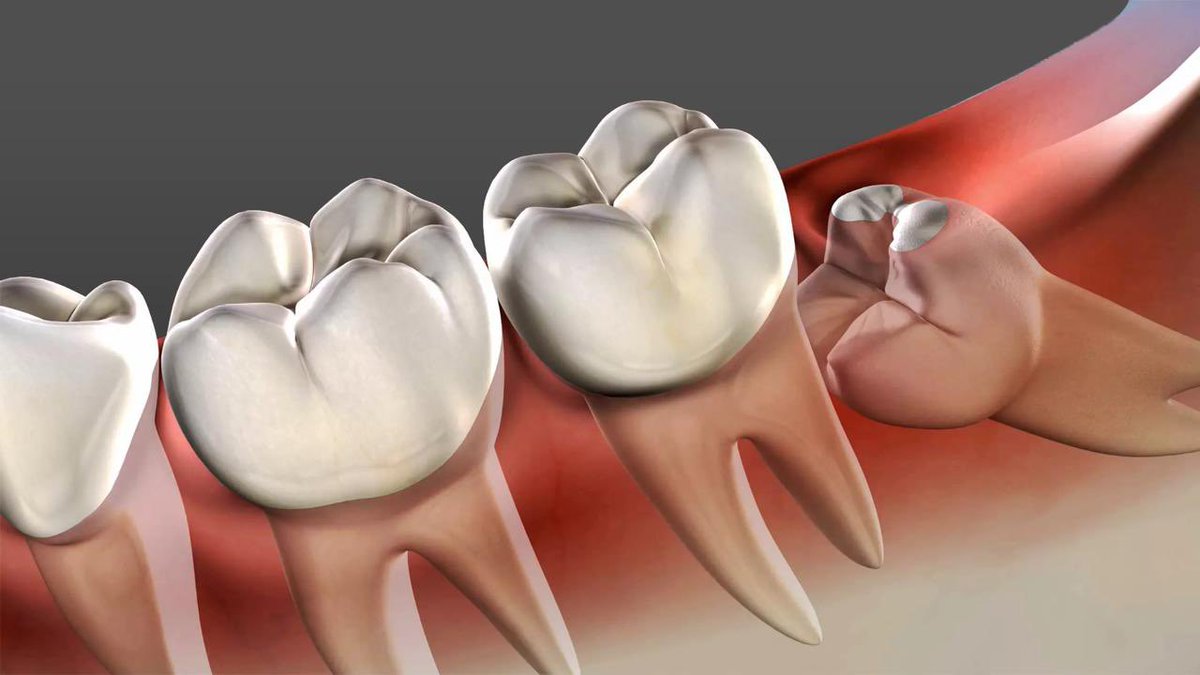

ونظراً لأنها اخر الأسنان التى تظهر بالفم ففى اغلب الاحيان لاتجد لها مكاناً بالفم وبالتالى

إما ان تظل مدفونة فى عظام الفك كلية ، أو تحاول البزوغ جزئياَ، أى يظهر جزء منها بالفم والباقى مدفوناَ بعظام الفك .

- قد ينمو ضرس العقل بصورة عرضية أو مائلة لاتسمح له بالظهور بالفك .

- عندما يكون ضرس العقل مائلاَ على الضرس المجاور يضغط عليه مسببا آلاما شديدة، وفى هذا الوضع المائل تتجمع فضلات الطعام محدثة تسوسا فى كل من الضرسين